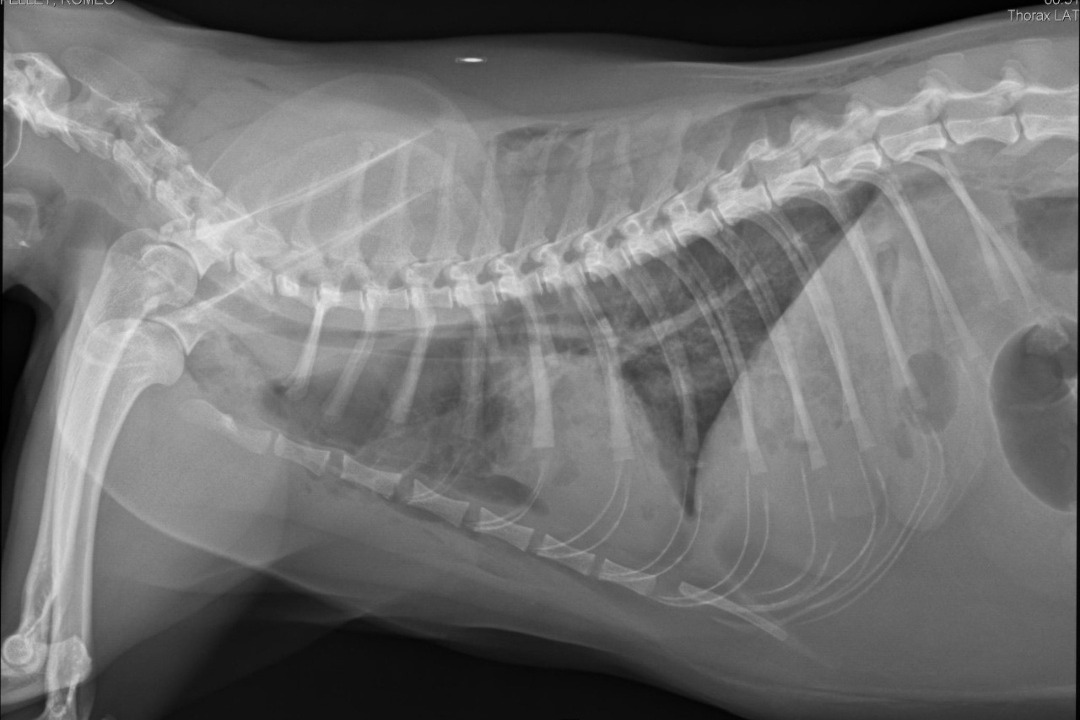

*Romeo's X-Rays*Our 4 year old cat Romeo has been SEVERELY injured and the vet stated that she believes he was crushed. When we came home after bringing him to the hospital, we realized that our boxspring was broken, so we believe that it fell onto him and crushed him. He has broken ribs, a shattered femur, etc. He will need to have his leg amputated, which in itself is $7000 and would be $17,000 if we decided to keep the leg and have them try to fix it and we genuinely cannot afford it.. And those prices are for his leg alone, it doesn't include the cost for his ribs or medications, or the $2000 a night to stay at the hospital. Please help us save our boy.. We cannot live in a world without him.. He's the most special cat in the entire world and our hearts are breaking. If we cannot afford the surgeries, then we will have to put him down. Please help in any way you can..